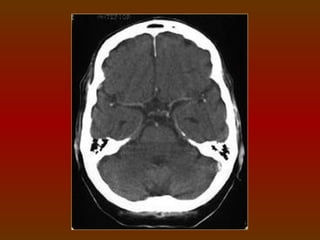

CORTE 5

a) Lobo frontal

b) Corno frontal do ventrículo lateral

c) Fissura silviana

d) Terceiro ventrículo

e) Glândula pineal (calcificada)

f) Plexo coróide (calcificado)

g) Lobo occipital